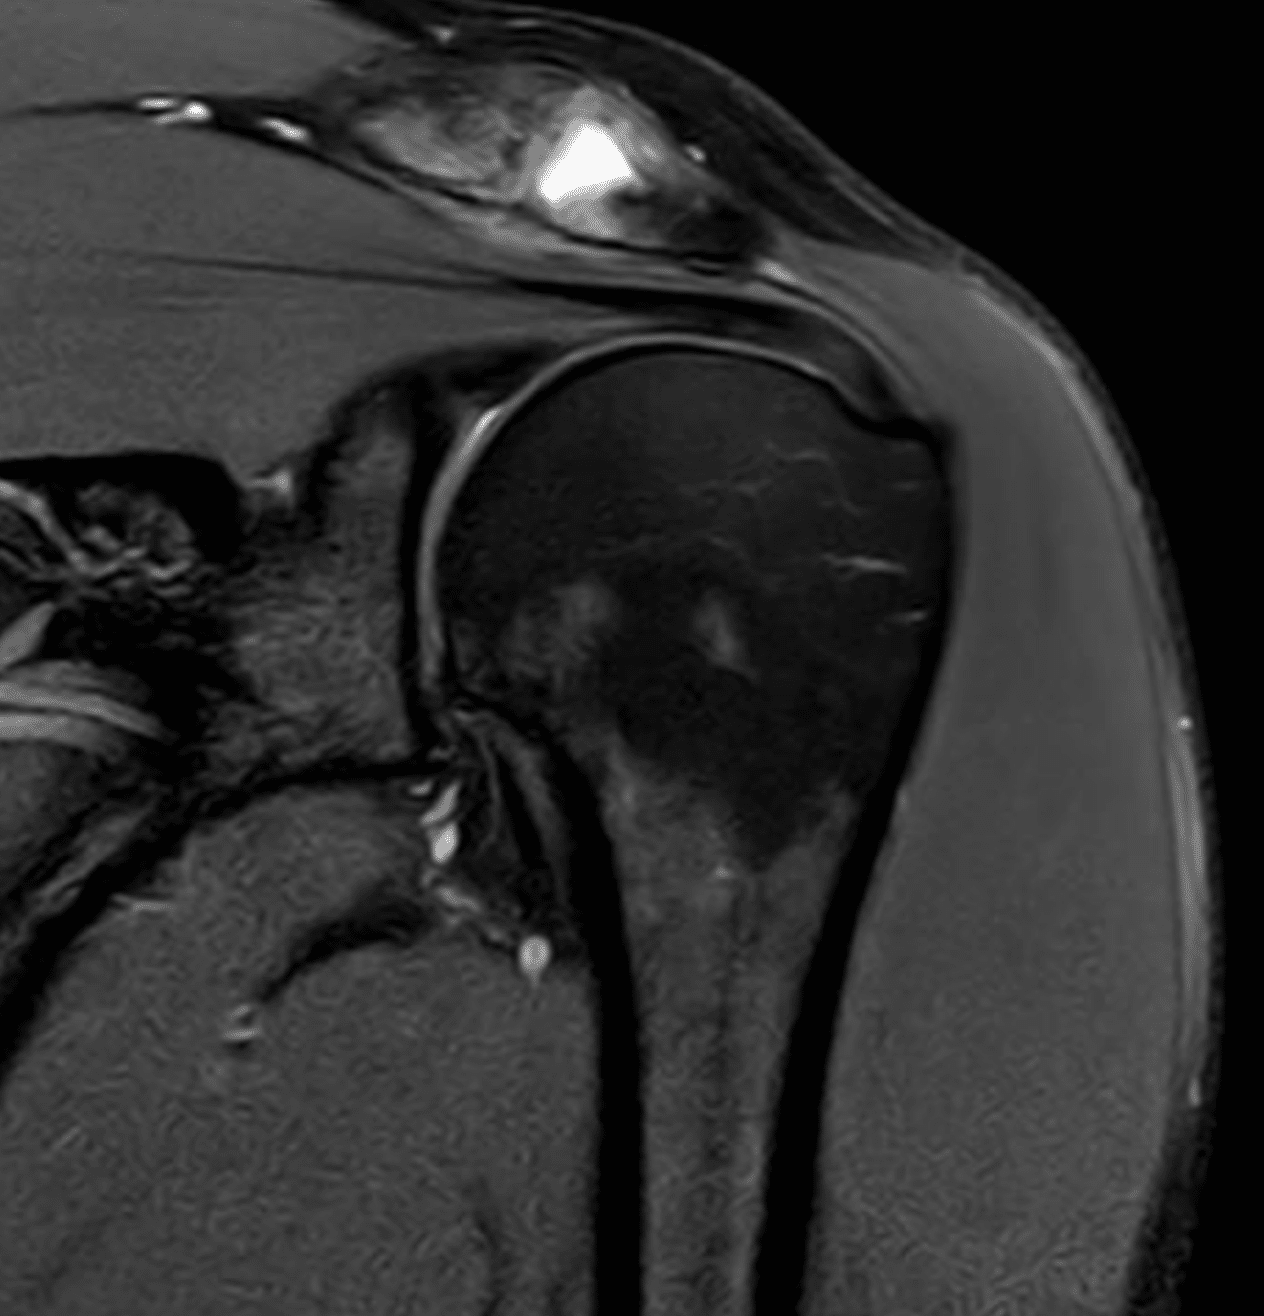

Die häufigste Ursache für Schulterschmerzen ist das Impingement-Syndrom – eine Enge unter dem Schulterdach, bei der Sehnen oder Schleimbeutel gereizt werden. Daneben zählen zu den relevanten Ursachen:

- Verletzungen der Rotatorenmanschette: Sehnenrisse oder Überlastung führen zu Bewegungseinschränkung und Schmerzen.

- Funktionelles Impingement: Entsteht durch muskuläre Dysbalancen, bleibt lange unbemerkt und führt über Entzündung (Tendinitis) und Sehnenansatztendinose zu Verkalkung und Schleimbeutelreizung (Bursitis subacromialis).

- Langfristige Folgen unbehandelter Fehlbelastung: Übergang in strukturelle Schäden mit möglichem Sehnenriss, vor allem des M. supraspinatus.

- Rekonstruktion der Rotatorenmanschette